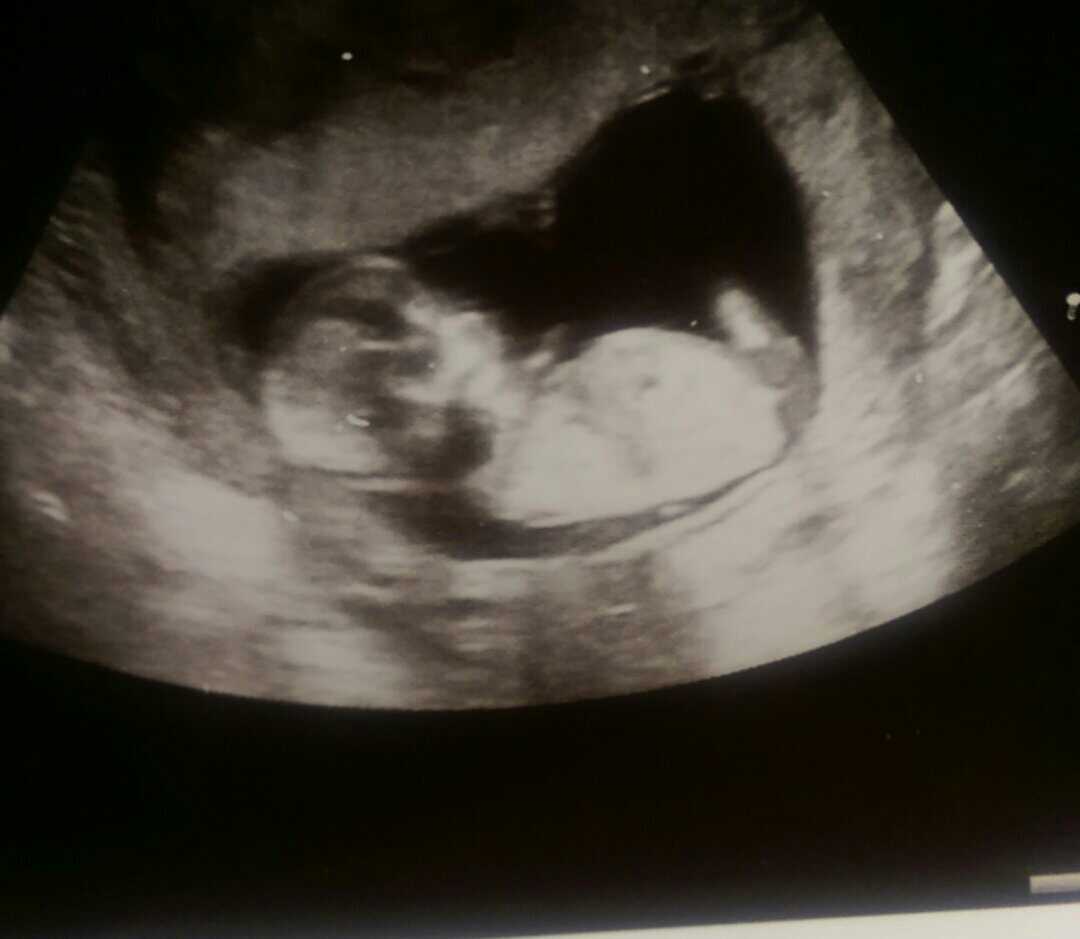

Any guesses for my 13 week nub shot please :)

Attachment 29303

Girly, I think?

A bit hard to tell but I'd guess girl.

Bekki it's not the clearest nub shot but I am going to guess girl!! I really hope we are right :fx: :fx:

I think it looks flat and girly. So sorry for your loss x

Another pic not sure it shows anything as am sure looks like cord between legs. Everytime I look at all 3 pics they seem to look different :(